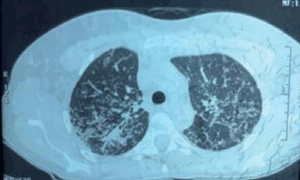

Durante la cirugía se realiza biopsia endomiocárdica y pulmonar que informa: proceso inflamatorio crónico granulomatoso sin necrosis, compatible con sarcoidosis a nivel pulmonar y cardíaco (figura 1) y (figura 2). Dado el compromiso cardíaco se indica metotrexate, con mala tolerancia digestiva, por lo cual se cambia a azatioprina 100 mg/día, tratamiento que recibe durante dos años. El paciente evoluciona asintomático, con estabilidad funcional respiratoria y cardiovascular a tres años del diagnóstico de SC.

Figura 3: TC: micronódulos pulmonares bilaterales cisurales y subpleurales, engrosamiento intersticial.